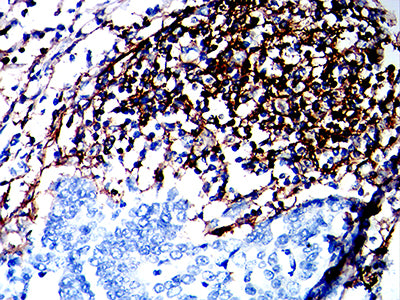

Immunohistochemical analysis of paraffin-embedded human Esophageal cancer tissues using CD180 mouse mAb with DAB staining.

Immunohistochemical analysis of paraffin-embedded human gastric cancer tissues using CD180 mouse mAb with DAB staining.